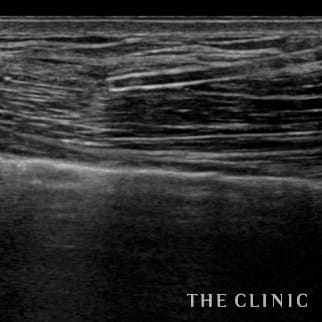

35歳 女性 アクアフィリング(アクアリフト)豊胸のお悩みのアクアフィリング(アクアリフト)豊胸除去

コンデンスリッチ豊胸を行うために、前もってアクアフィリングの除去を行いました。エコーで確認するとかなり厚い被膜が形成されています。 アクアフィリングは生理食塩水で溶解されるとのことで、エコー下に生理食塩水を注入しましたが、なかなか溶解できず、ヒアルロニダーゼも追加してなんとか溶解除去することができました。右側は炎症があった為か、汚く濁った状態でした。治療の概要 アクアフィリング除去+コンデンスリッチ豊胸:乳腺用エコーを用いて、バスト内の状態を確認。その後、生理食塩水でアクアフィリングを溶解する。溶解仕切れない場合には、注射器で吸い出し除去。アクアフィリング の除去後、バストの皮下にコンデンスリッチファット(老化細胞や不純物を取り除いて濃縮させた自己脂肪)を注入。 施術費用 アクアフィリング 除去(会員料金):¥600,000(税込¥660,000)/溶解1部位

コンデンスリッチ豊胸(モニター価格):¥880,000〜(税込¥968,000〜)